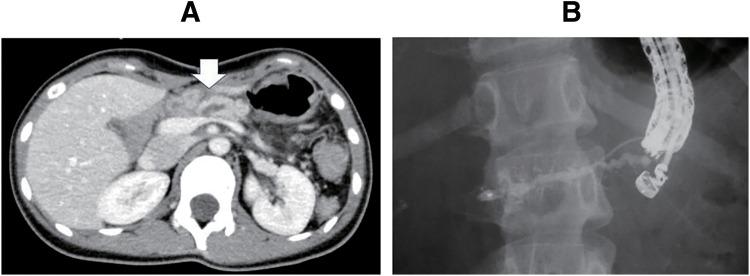

A 20-year-old woman underwent laparoscopic pancreaticoduodenectomy for a solid pseudopapillary neoplasm in the pancreatic head. During the follow-up, she presented with recurrent abdominal pain, elevated pancreatic enzymes, and dilation of the main pancreatic duct, suggestive of a remnant pancreatitis secondary to pancreaticojejunostomy stenosis. Endoscopic evaluation using double-balloon endoscopy failed to locate the anastomosis. Endoscopic ultrasound enabled puncture and cannulation of the main pancreatic duct, though the anastomotic site remained obstructed. An endoscopic nasal pancreatic drainage tube was placed within the main pancreatic duct. Subsequently, open surgery was performed to dilate the anastomosis and insert a drainage tube. A gastrotomy was created, revealing a fistula between the stomach and pancreas, and a guidewire was introduced from the fistula to the anastomosis. The guidewire was inserted through the fistula and guided to the jejunum through the anastomosis by incising the jejunum on the opposite side of the pancreaticojejunostomy. A stent was deployed across the anastomosis, and a transgastric pancreatic duct drainage was made. The patient subsequently underwent endoscopic dilation and is currently asymptomatic.

一名20岁女性因胰头部实性假乳头状瘤接受了腹腔镜胰十二指肠切除术。在随访期间,她出现反复腹痛、胰酶升高以及主胰管扩张,提示胰肠吻合口狭窄继发的残余胰腺炎。使用双气囊内镜进行的内镜评估未能找到吻合口。内镜超声能够穿刺并插入主胰管,但吻合口部位仍阻塞。在内镜引导下将鼻胰引流管放置于主胰管内。随后,进行了开放手术以扩张吻合口并插入引流管。创建了胃切开术,发现胃与胰腺之间存在瘘管,并从瘘管插入导丝至吻合口。导丝通过瘘管插入,并通过在胰肠吻合口另一侧切开空肠,经吻合口引导至空肠。在吻合口处放置了支架,并进行了经胃胰管引流。患者随后接受了内镜扩张,目前无症状。